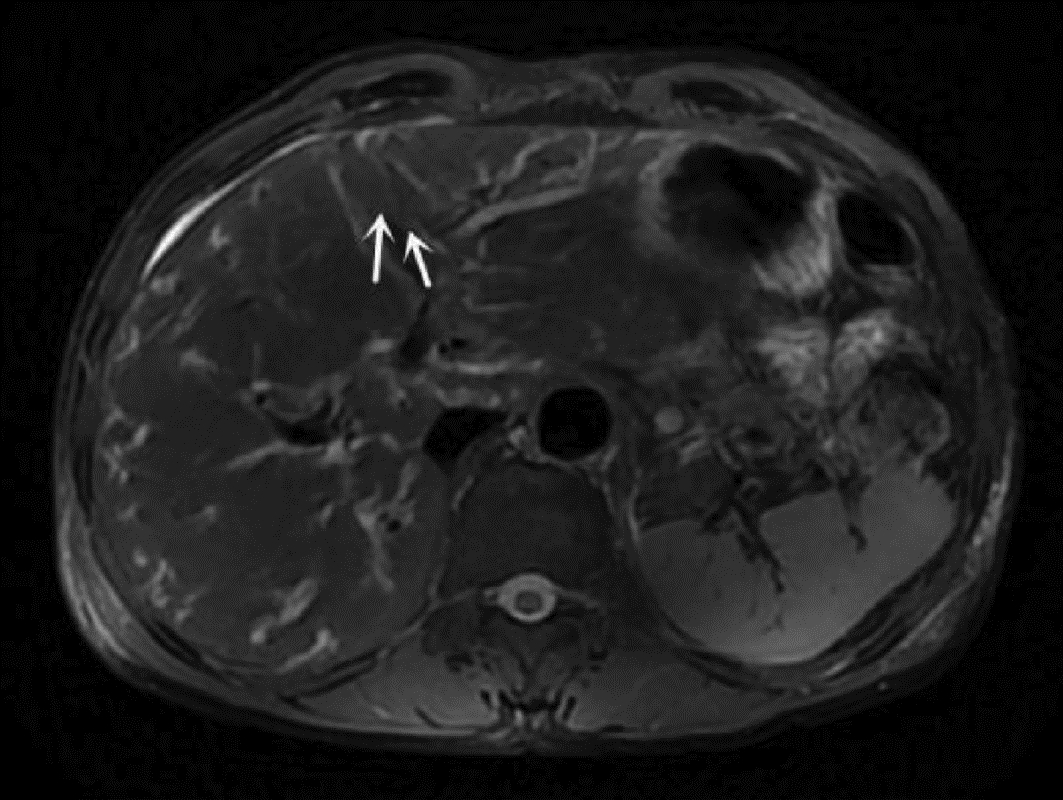

Hepatitis B cirrhosis with hepatic paragonimiasis misdiagnosed as primary liver cancer: A case report

Shenfeng HUANG, Jiajun LIN, Yang TAN, Zhifang CAI

2022, 38(6): 1367-1369. DOI: 10.3969/j.issn.1001-5256.2022.06.028

Abstract(985) HTML (273) PDF (2412KB)(52)

Abstract: